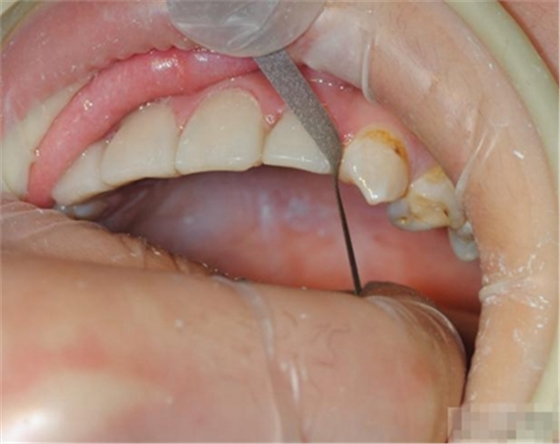

【主訴】上前牙充填物脫落兩個(gè)月

【病史】上前牙一年前行根管治療,充填物部分脫落,自覺(jué)影響美觀,從不敢笑,要求先行樹(shù)脂修復(fù)。(年齡:14歲)

【檢查】12,11,21,22,均行玻璃離子充填,各牙不同程度部分充填物脫落,探(—),叩(—),冷刺激無(wú)反應(yīng),無(wú)松動(dòng),牙齦顏色粉紅,質(zhì)地堅(jiān)實(shí)而有彈性,點(diǎn)彩正常,牙結(jié)石(—);牙髓活力測(cè)試無(wú)反應(yīng)。

【診斷】12,11,21,22牙體缺損